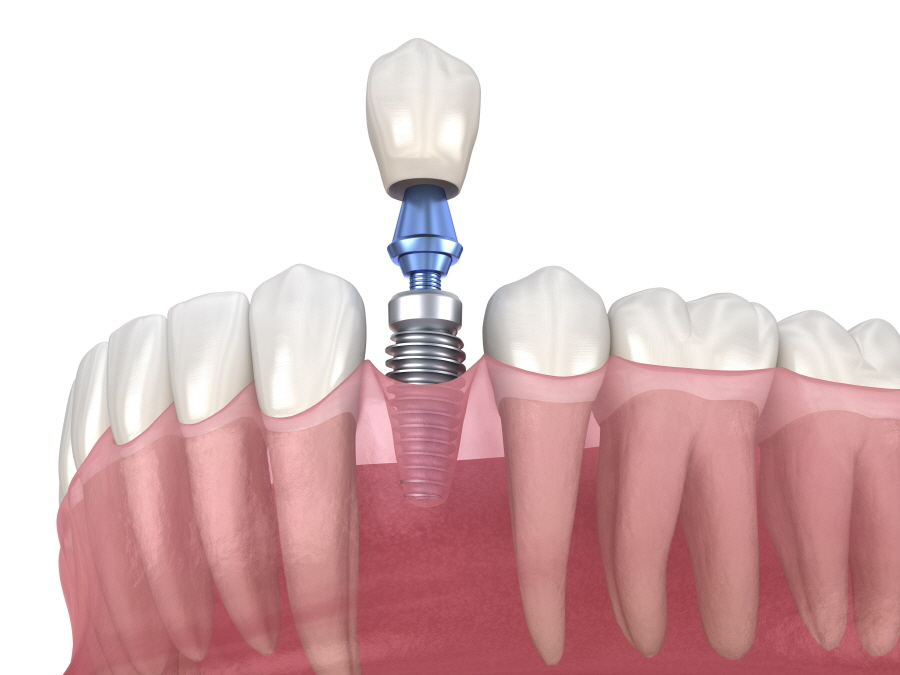

임플란트는 자연치아가 상실되었을 때

치아의 기능을 대신할 수 있는

치료방법으로 잇몸뼈에 구조물을

직접 심는 방식으로 진행됩니다.

임플란트의 구조는 세 가지로

나누는데 치아의 뿌리 역할을

하는 인공 뿌리(fixture),

인공 뿌리와 보철물을 연결해 주는

중간 기둥 역할의 지대주(abutment),

치아 모형의 최종 보철물(crown)로

나누어지며, 기존의 틀니나 브릿지에